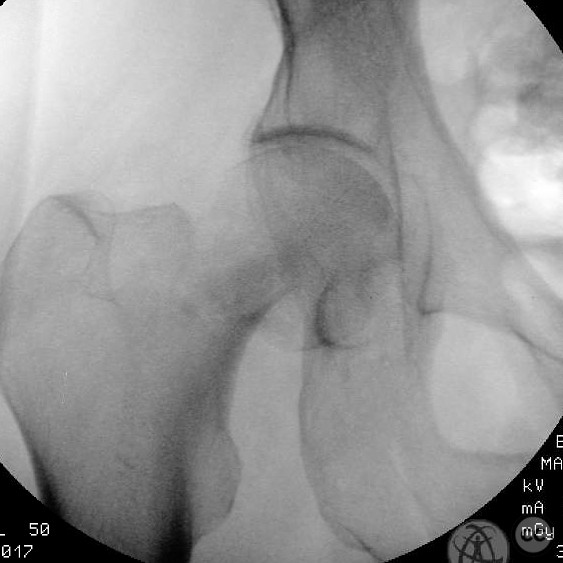

Clinical and radiological findings:  A 62-year-old male presented following a fall from standing height, resulting in a displaced subcapital femoral neck fracture. The patient has a complex medical history including substance abuse (methamphetamine and cocaine), cirrhosis, diabetes, and open draining foot wounds. Radiographs confirmed a displaced femoral neck fracture, classified as AO/OTA 31-B2.

Patient positioning:  The patient was positioned supine on a fracture table to facilitate closed reduction and percutaneous fixation under fluoroscopic guidance.

Anatomical surgical approach:  A percutaneous approach was utilized, involving small stab incisions for the insertion of guide wires and cannulated screws. Fluoroscopic imaging was employed to ensure proper alignment and fixation.

The surgeon emphasized the importance of achieving an anatomical reduction and avoiding varus malalignment during fixation. The decision to pursue percutaneous fixation was influenced by the patient's high risk for complications with arthroplasty due to his comorbidities and lifestyle factors. The potential for conversion to hemiarthroplasty was considered if fixation failed.